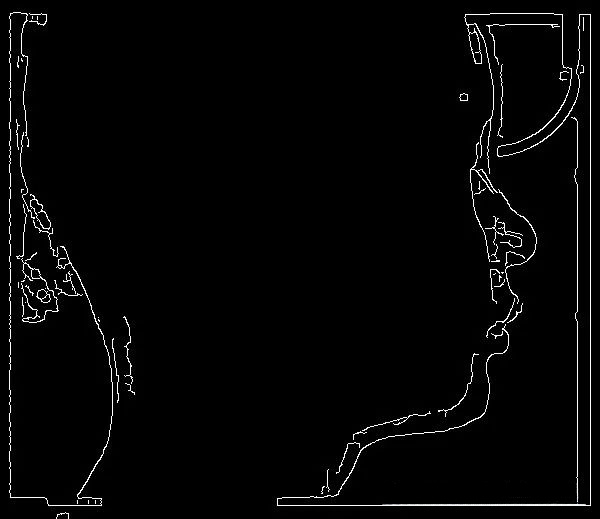

二、基于边缘检测的方法

1、梯度算子:Sobel 算子

Sobel 算子是一种常用的边缘检测算子,广泛应用于图像处理和计算机视觉领域。它通过计算图像在水平和垂直方向上的梯度来检测图像中的边缘。Sobel 算子不仅能够突出图像中的边缘,还能抑制噪声的影响,因此在实际应用中非常受欢迎。Sobel 算子的基本思想是利用卷积核(也称为滤波器)在图像上滑动,计算每个像素点在水平和垂直方向上的梯度值。具体步骤包括:首先,定义两个3x3的卷积核,一个用于检测水平方向的边缘,另一个用于检测垂直方向的边缘。

Sobel 算子在多种图像处理和计算机视觉任务中都有广泛的应用,包括但不限于边缘检测、图像增强、运动检测和医学成像。在边缘检测中,Sobel 算子是最经典的边缘检测方法之一,能够有效地检测图像中的边缘,广泛应用于图像分割、特征提取等任务。在图像增强中,通过增强图像的边缘信息,Sobel 算子可以改善图像的视觉效果,使其更加清晰。在视频监控和运动检测中,Sobel 算子可以用来检测帧间的边缘变化,从而识别运动物体。在医学图像处理中,Sobel 算子可以用于检测组织结构的边界,辅助医生进行诊断。

2、Canny 边缘检测器